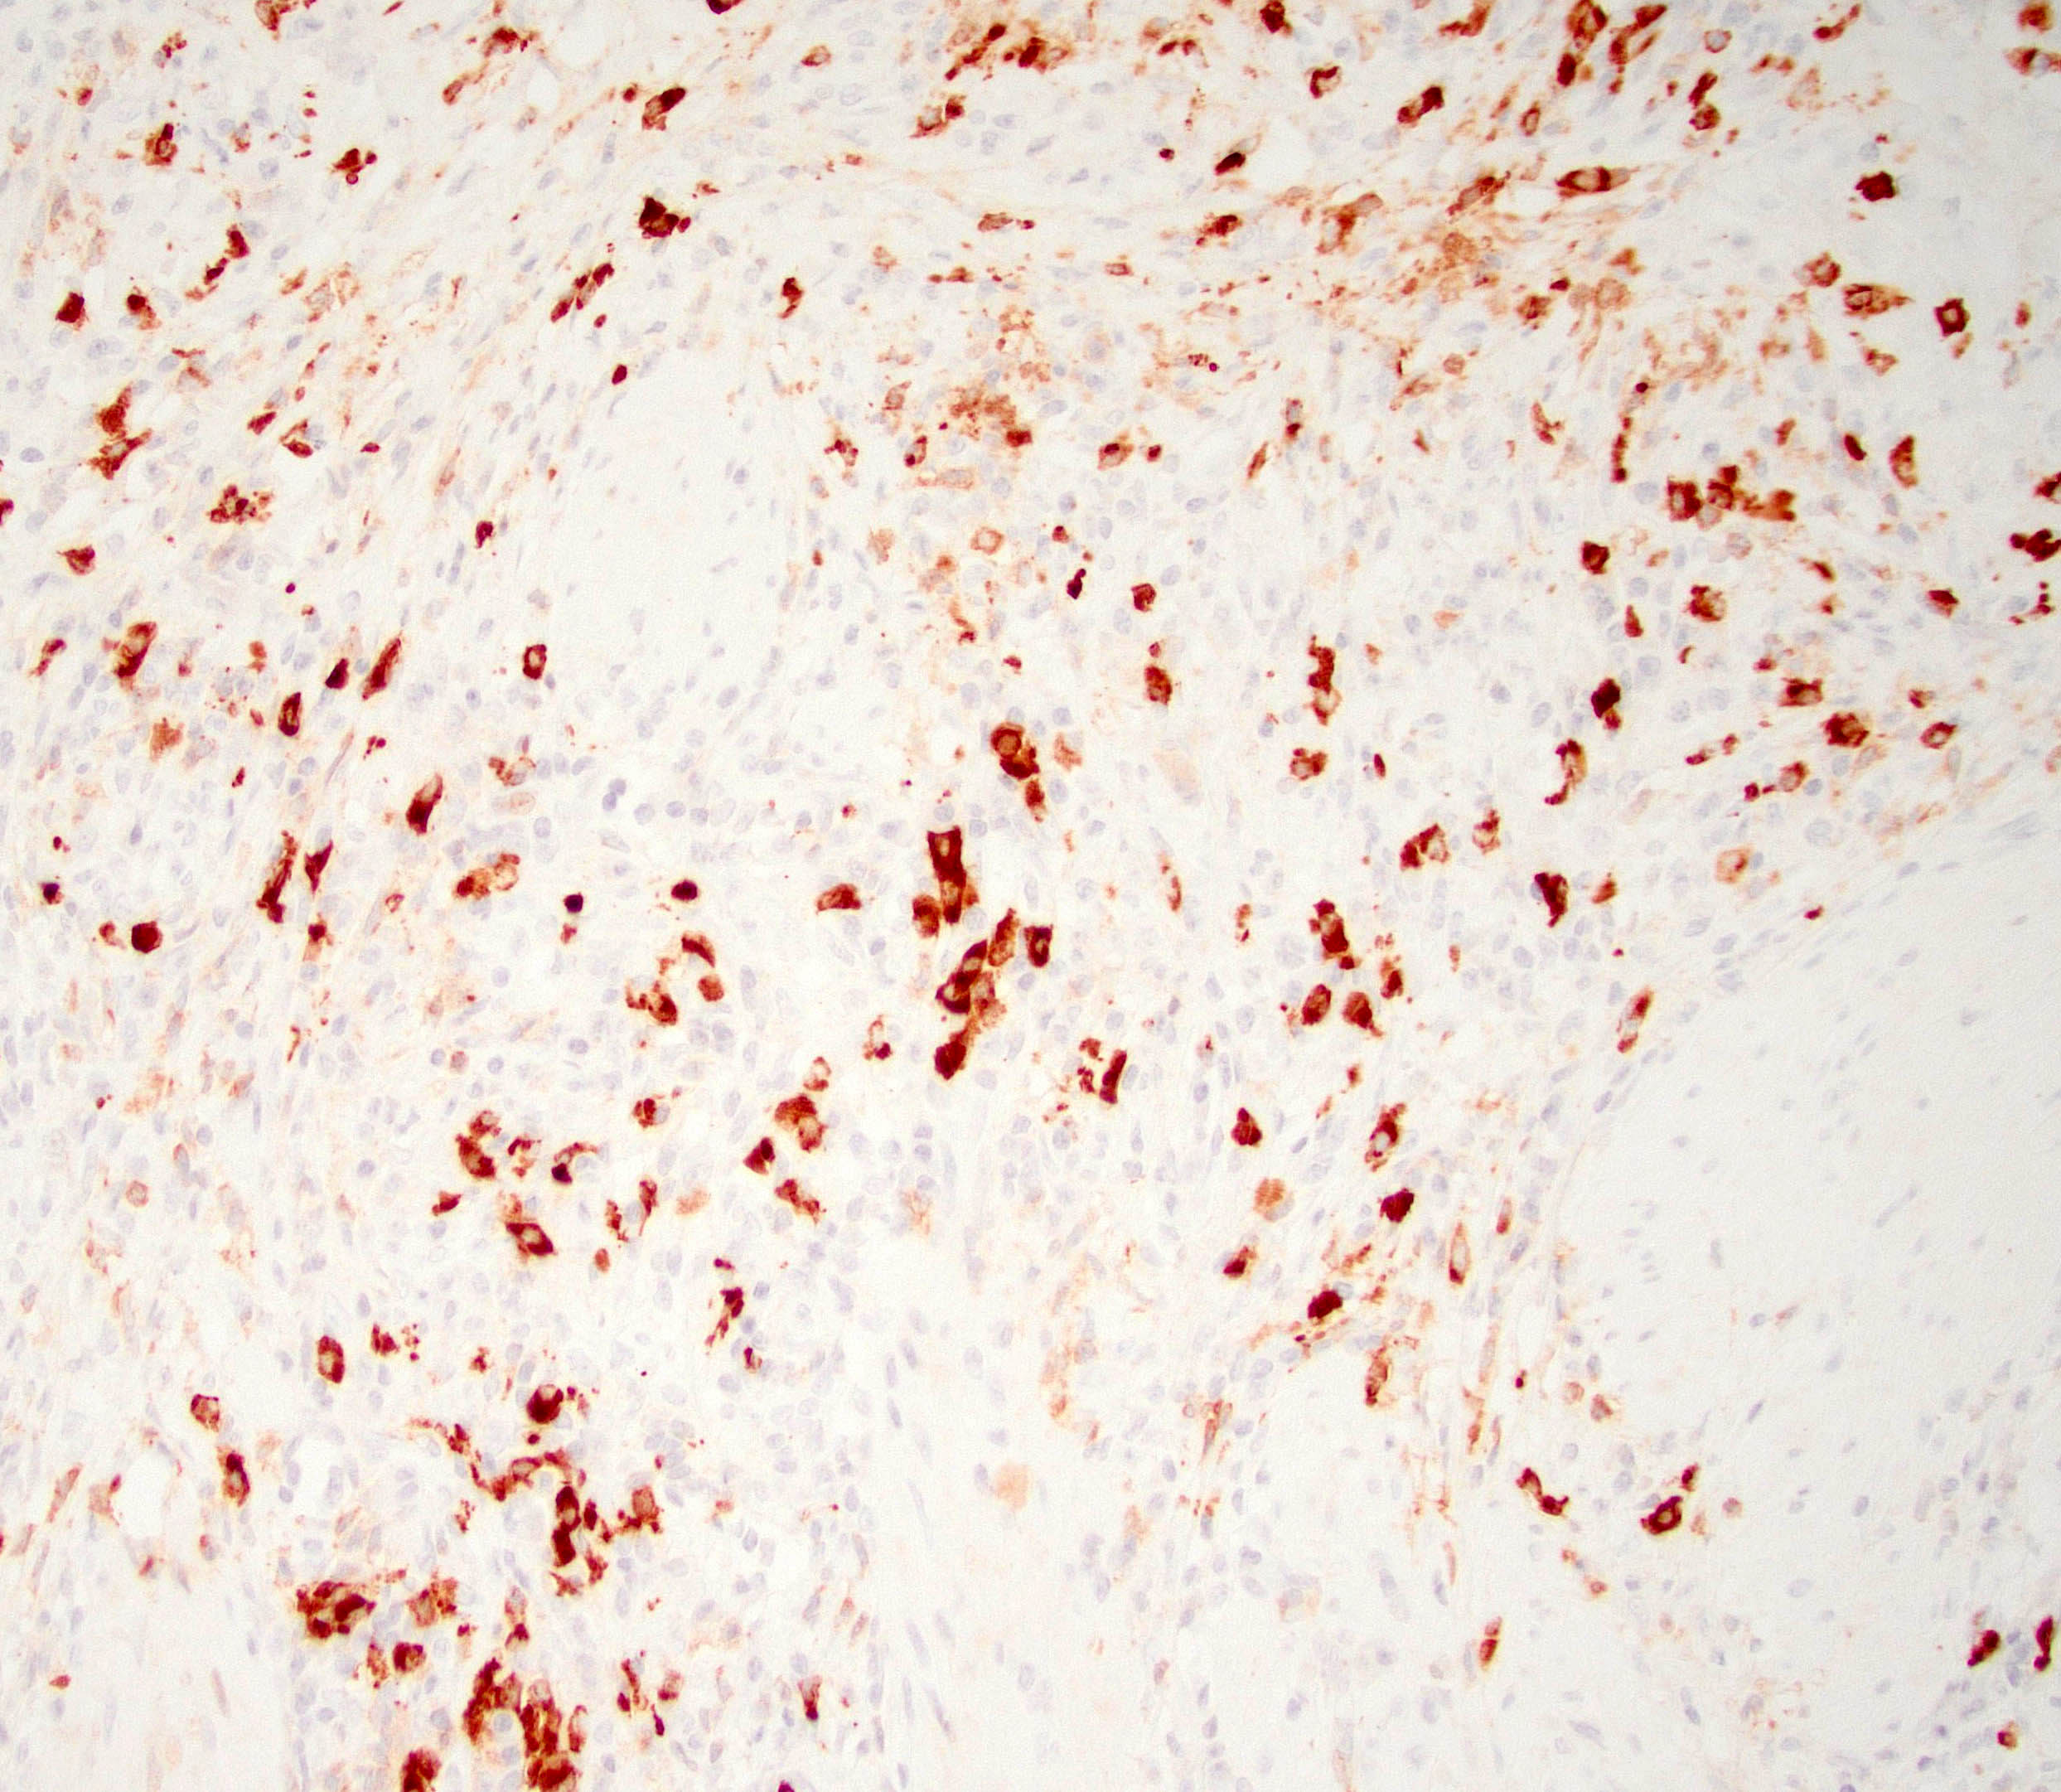

Positive stains

- IgG and IgG4

- > 10 IgG4 positive cells per high power field in biopsy specimens (Pancreas 2011;40:352)

- > 50 IgG4 positive cells per high power field in resection specimens (Virchows Arch 2018;472:545)

- IgG4/IgG ratio > 40% (Virchows Arch 2018;472:545)

- Elastic: highlights remnant veins in longstanding autoimmune pancreatitis

- Masson trichrome: highlights storiform fibrosis

- Comment: H&E sections demonstrate pancreatic parenchyma with dense storiform fibrosis and numerous chronic inflammatory cells including abundant plasma cells. A partially obliterated vein is seen. Immunohistochemical stain for IgG4 shows increased IgG4 positive plasma cells (up to 20 - 25 per high power field). The combined findings are most consistent with autoimmune pancreatitis type 1.